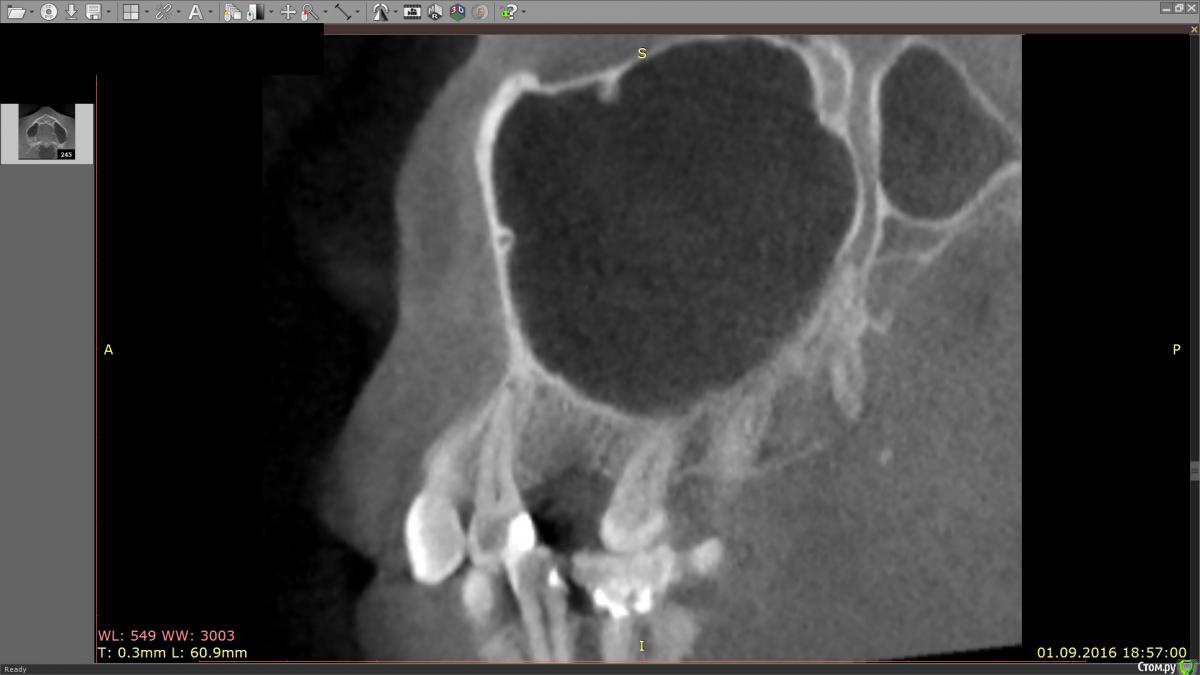

marinamarina Опубликовано 16 октября, 2016 Автор Поделиться Опубликовано 16 октября, 2016 (изменено) Прилагаю фрагмент КТ. Изменено 16 октября, 2016 пользователем marinamarina Ссылка на комментарий

IvanK Опубликовано 17 октября, 2016 Поделиться Опубликовано 17 октября, 2016 Большая вероятность того, что какой-то вид наращивания кости потребуетсянужно оценить не только высоту костной ткани до верхнечелюстной пазухи, но и ширину Ссылка на комментарий

marinamarina Опубликовано 17 октября, 2016 Автор Поделиться Опубликовано 17 октября, 2016 Большая вероятность того, что какой-то вид наращивания кости потребуетсянужно оценить не только высоту костной ткани до верхнечелюстной пазухи, но и ширинуСпасибо за ответ! Про синус лифтинг я знаю, я имею в виду пересадку костного блока в место травмы, попробую выложить поперечный срез. Ссылка на комментарий